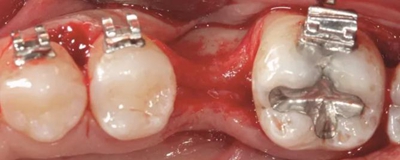

經(jīng)過最初1年的正畸排齊后,右側(cè)下頜第一磨牙無牙區(qū)的近遠中距離由6mm增至7mm,左側(cè)下頜第一磨牙的近遠中距離由7mm增至8mm(圖4)。取得患者知情同意后,采用與病例1中描述的相同技術(shù)和材料進行同期牙槽嵴增量和加速磨牙直立程序(圖5a-5g)。除了右側(cè)磨牙后區(qū),在右側(cè)第二和第三磨牙根部之間也進行了去皮質(zhì)術(shù)(圖5d)。骨增量術(shù)后,即刻將0.016×0.022 英寸帶有30° 后傾彎的鈦鉬合金絲(Dentsply)置于兩側(cè)。6周后,以半個托槽的距離進行主弓絲套推簧雙側(cè)輕加力(圖5h)。

術(shù)后3個月,右側(cè)第一磨牙的空間約為9mm(3個月中增加了1.6mm),逐漸接近了對側(cè)第一磨牙的空間(也約9mm)(圖6a)。術(shù)后7個月的錐束CT顯示,右側(cè)第一磨牙區(qū)域獲得了2.5mm的水平骨增量(圖6b 和c)。左側(cè)第一磨牙的無牙區(qū)保持相同的尺寸,在種植體植入前也需要骨增量。

圖6a.病例2中,右下第一磨牙種植位點獲得了成功的骨增量和加速磨牙直立。治療3個月后,第一磨牙種植位點增加了1.6mm 的近遠中修復空間,并獲得了顯著的骨增量。對側(cè)位點,左下第一磨牙,仍需要在種植體植入前進行額外的骨增量